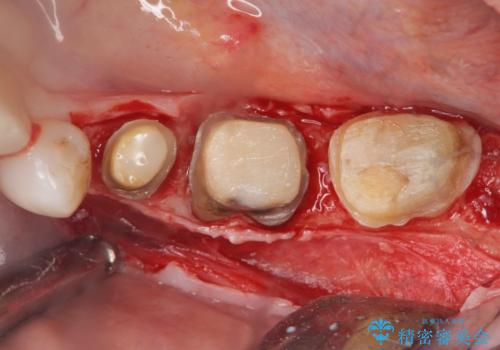

クラウンやレジン下に再発していた虫歯を丁寧に除去したのち、歯ぐきの腫れが改善が見られないため歯周外科を行い歯ぐきの状態を整えたのちにジルコニアクラウンを製作していきます。

クラウン治療を行う場合歯ぐきの腫れが、クラウン製作の精密さにおいて問題点となることがあります。

このような場合、歯周外科を行うことでクラウン周囲の歯茎の状態を整備し精度に優れる治療を行うことができます。